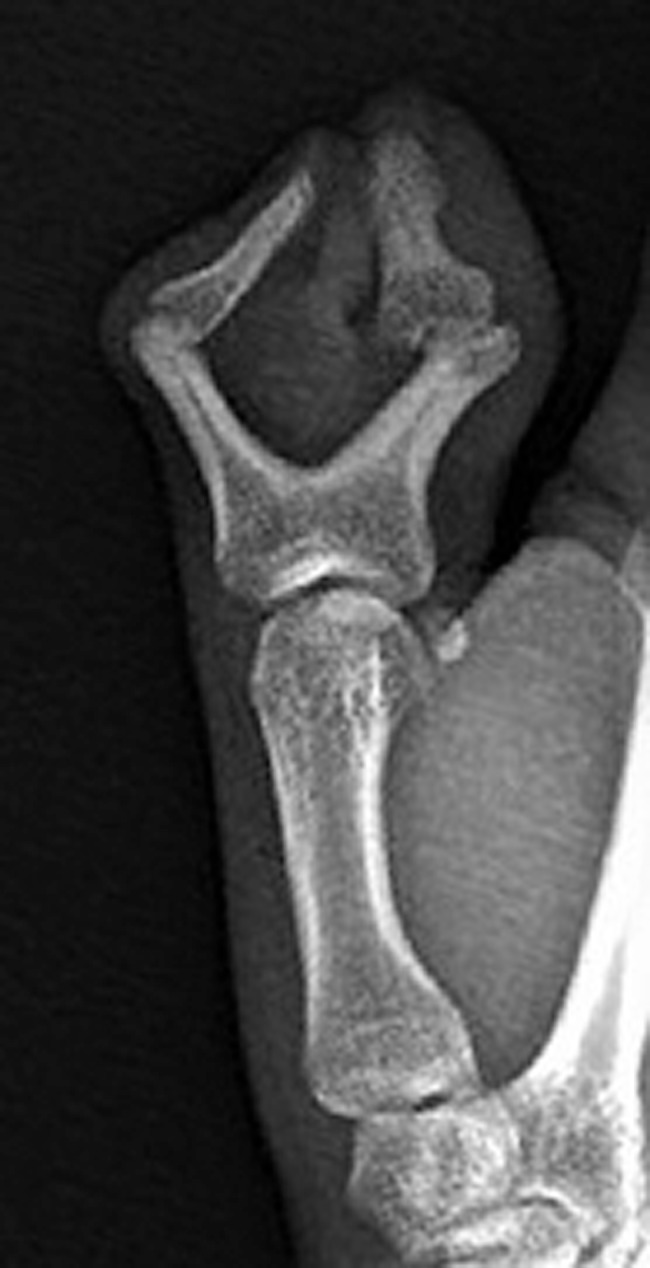

Fig. 4.

Anteroposterior radiograph of the right thumb demonstrates bifid proximal phalanx and duplication of the distal phalanx of the thumb consistent with Wassel type III polydactyly.